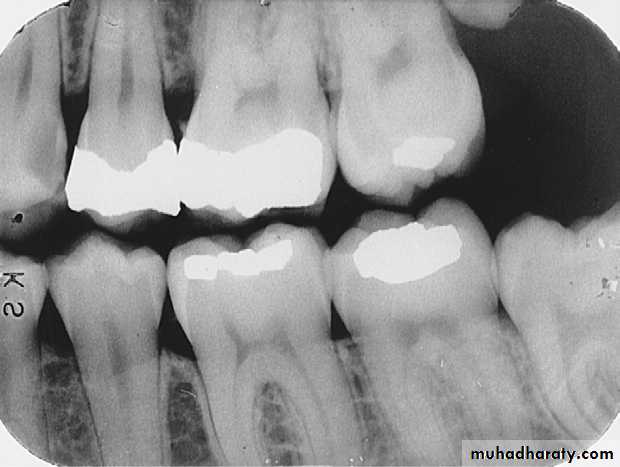

just below the cemento-enamel junction (CEJ) on the mandibular second premolar.Found around the margins of existing restorations. May be due to;

Recurrent Caries

Recurrent caries seen as a radiolucency below a two surface amalgam restoration on the mandibular second premolar.